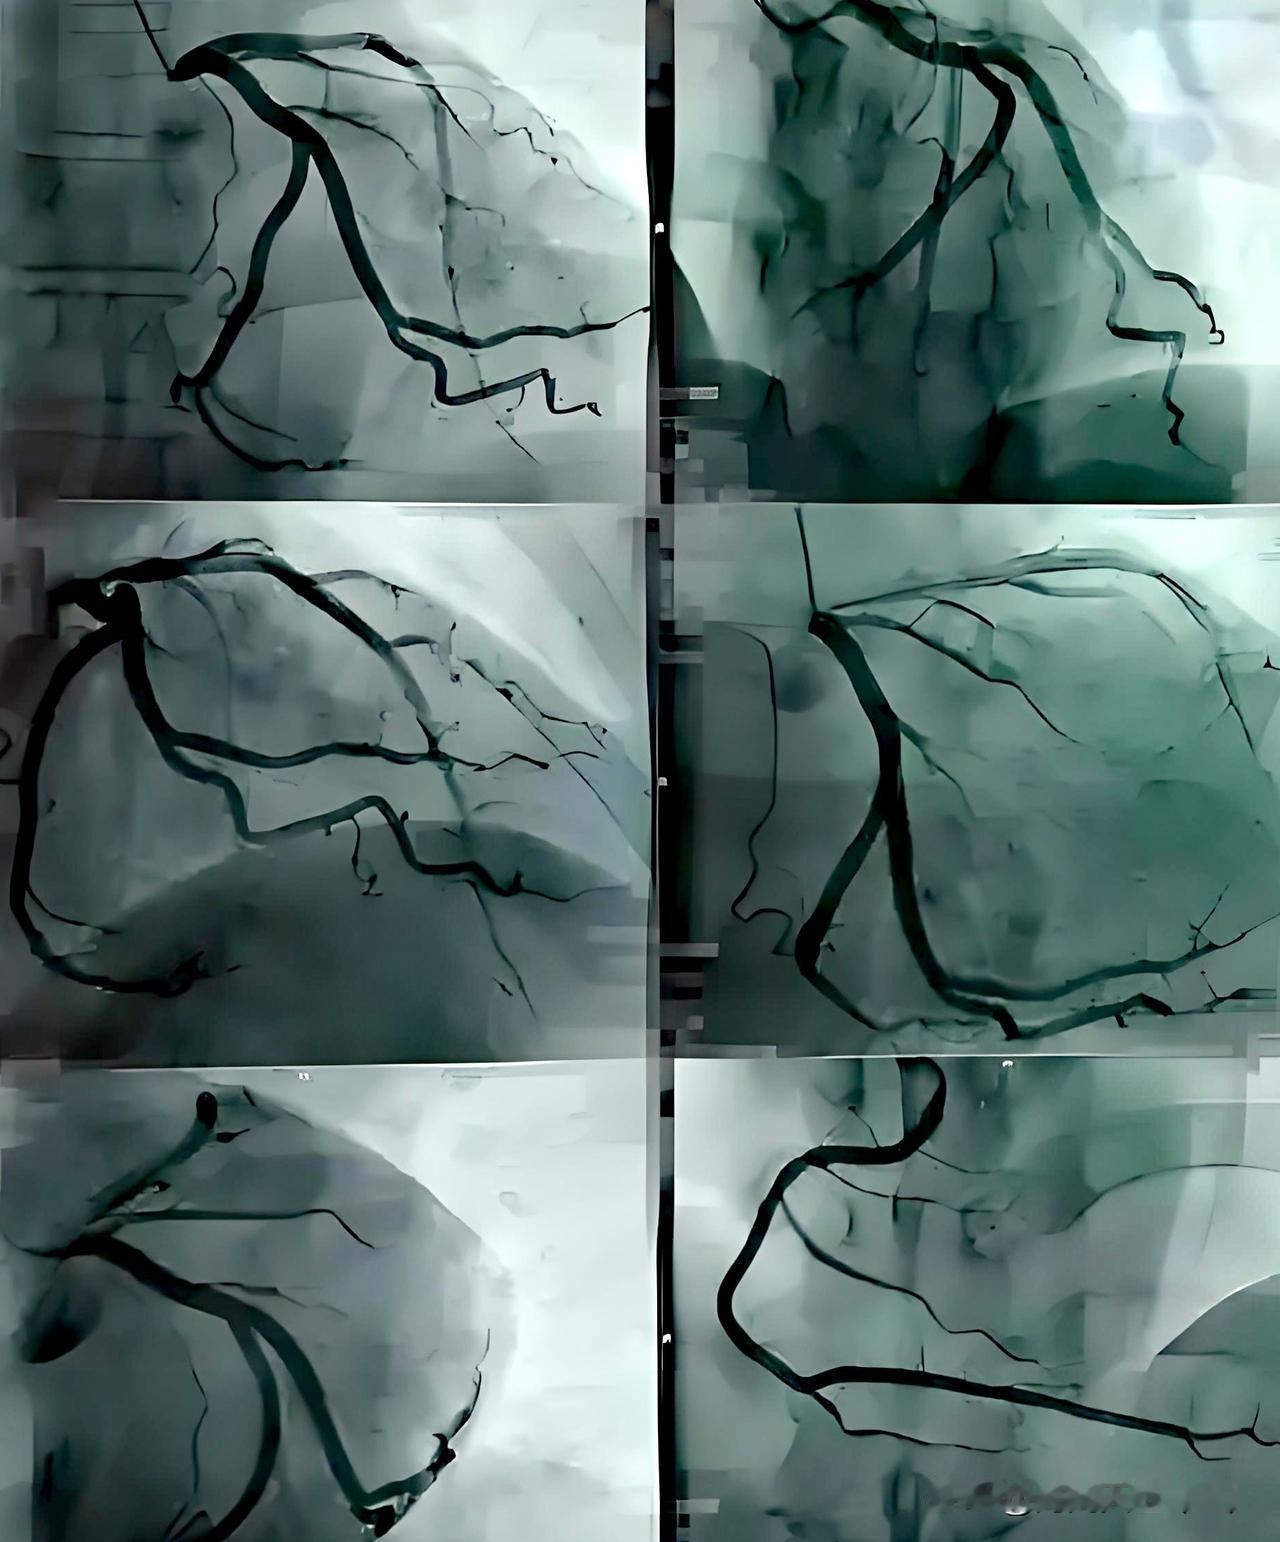

一个选择性体检~冠脉CTA检查,带来的麻烦事! 我们单位福利很好,每年都会会每位员工2000多元的体检,由于体检的人多,医院也给我单位一定的优惠,这样每位员工体检的项目和部位就挺多! 我一个单位同事好朋友,去年体检,发生了一些曲折,他认为我医学知识懂的比较多,于是向我倾诉了他的心事!单位体检有多选项目,他问体检医生,多选项目做什么?医生告诉了他可选择的项目,并问他选择哪项?他倾向于选择冠脉CTA,医生同意,于是做了冠脉CTA,结果显示:心脏冠状动脉前降支有一段有中度狭窄,并有钙化斑块,其余多轻度狭窄,也有些部位钙化斑块! 体检医生通知了他,让他找心血管医生,他特意找了个心血管专家看,这位专家让他吃药,每晚服一片10mg的瑞舒服他汀钙片降血脂,并嘱咐把低密度脂蛋白胆固醇降到1.8mmol/L以下,于是他吃该药一段时间后检查,低密度脂蛋白胆固醇未达1.8mmol/L以下,因此,他又找了另一个专家开依折麦布,继续降低低密度脂蛋白胆固醇,结果这位年纪大一点的专家却极力建议他做冠脉造影,说冠脉CTA不准确,是银标准,冠脉造影才准确,是金标准! 我这位朋友查阅了很多资料,又在网上看了一些医生的视频讲解,说做冠脉CTA有碘过敏、血管损伤可诱发慢性炎症等副作用,不要随便做,还有,我单位也有另一位同事做了冠脉CTA,也有血管中度狭窄,也有医生让他做造影,造影后,结果是示狭窄为轻度,于是不当做冠心病治,让其出院了! 我这位朋友也担心出现冠脉CTA可能误诊夸大狭窄的问题和冠脉造影的副作用,但偶尔也发生静坐沙发左胸闷有一会弊闷不适的感觉,但快走3~6公里,也从未出现不适,经再三思考,并咨询了一些其它医生,他决定不做冠脉造影,而把自已当普通冠心病治,后又每晚吃20mg阿托伐他汀钙片(有医生说,药理试验有明确降低冠心病发作作用,并写入说明书,而瑞舒伐他汀钙片降脂未做过此类试验,于是改服)、10mg依折麦布降血脂,吃了一年,防止冠脉狭窄加重,后期加早晨一片10mg阿司匹林,防止冠脉形成血栓凝集、加一片47.5mg的琥珀酸美托洛尔缓释片,降低心率和心肌缺血症状,吃了也有半年多,期间多次检查血脂,低密度脂蛋白胆固醇均未超过1.8mmol/L,其余指标均未超标,但我这位同事朋友仍很纠结,到底要不要听那位年纪大点的专家建议,做冠脉造影? 思来想去,他把问题发deepseek询问,结果deepseek完全赞成他这个决定,只治疗暂不做冠脉造影,并密切观察症状和医生沟通,还可做运动平板心电图、负荷超声心动图 或 心肌灌注显像,以进一步根据症状反应和心肌是否缺血,辅助判断心肌供血是否存在问题。还建议静息情况心,心闷等症状频繁发作,有劳力性心绞痛症状发作时,再考虑做冠脉造影! 唉,我这位同事朋友感觉看一个病好难,太麻烦、太难选择!医生的分歧还这么大,让病人为了难!还要自己判断该不该做进一步检查,以准确明确病征!太挠头了! 选择性体检项目 冠脉CTA检查